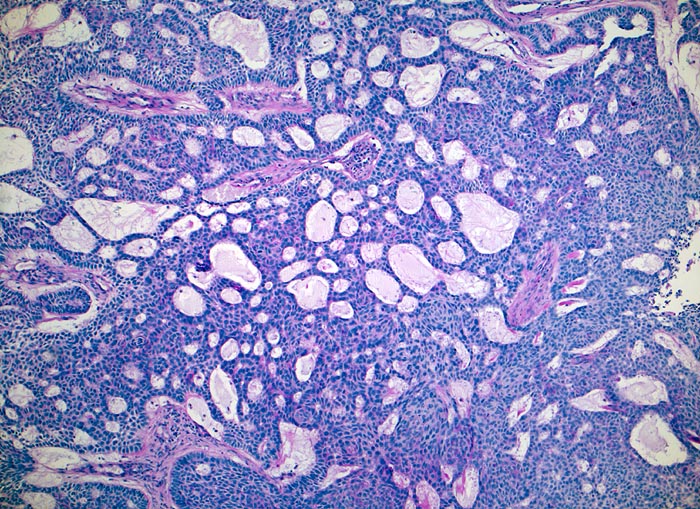

PathoPic – image database / PathoPic ID 3947 - adenoides Basalzellkarzinom

adenoides Basalzellkarzinom

Das Basalzellkarzinom zeigt innerhalb solider monomorpher Zellplatten zahlreiche an Drüsen erinnernde Hohlraumbildungen ähnlich einem adenoidzystischen Karzinom. In den Randbereichen der Zellplatten ist die typische Palisadierung der Tumorzellen erkennbar.

Histologie

Vergrösserung